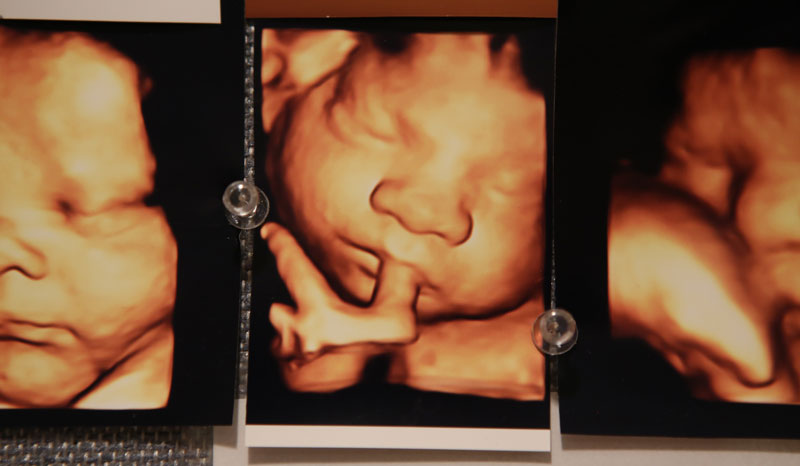

Barberic, Burnett and Kemppel have seen facial expressions as early as 14 weeks.

“I’ve seen every kind of expression, from smiling and laughing to mad, crying looking,” Burnett said.

They’ve also all seen the tongue-out, raspberry-like facial expression.

Dr. Nadja Reissland, a researcher and psychologist who specializes in fetal development at Durham University, found that younger fetuses make spontaneous expressions while older ones hold those expressions. She suggests these expressions are not a sign of emotion but a form of practice as the fetus prepares to enter the social world.